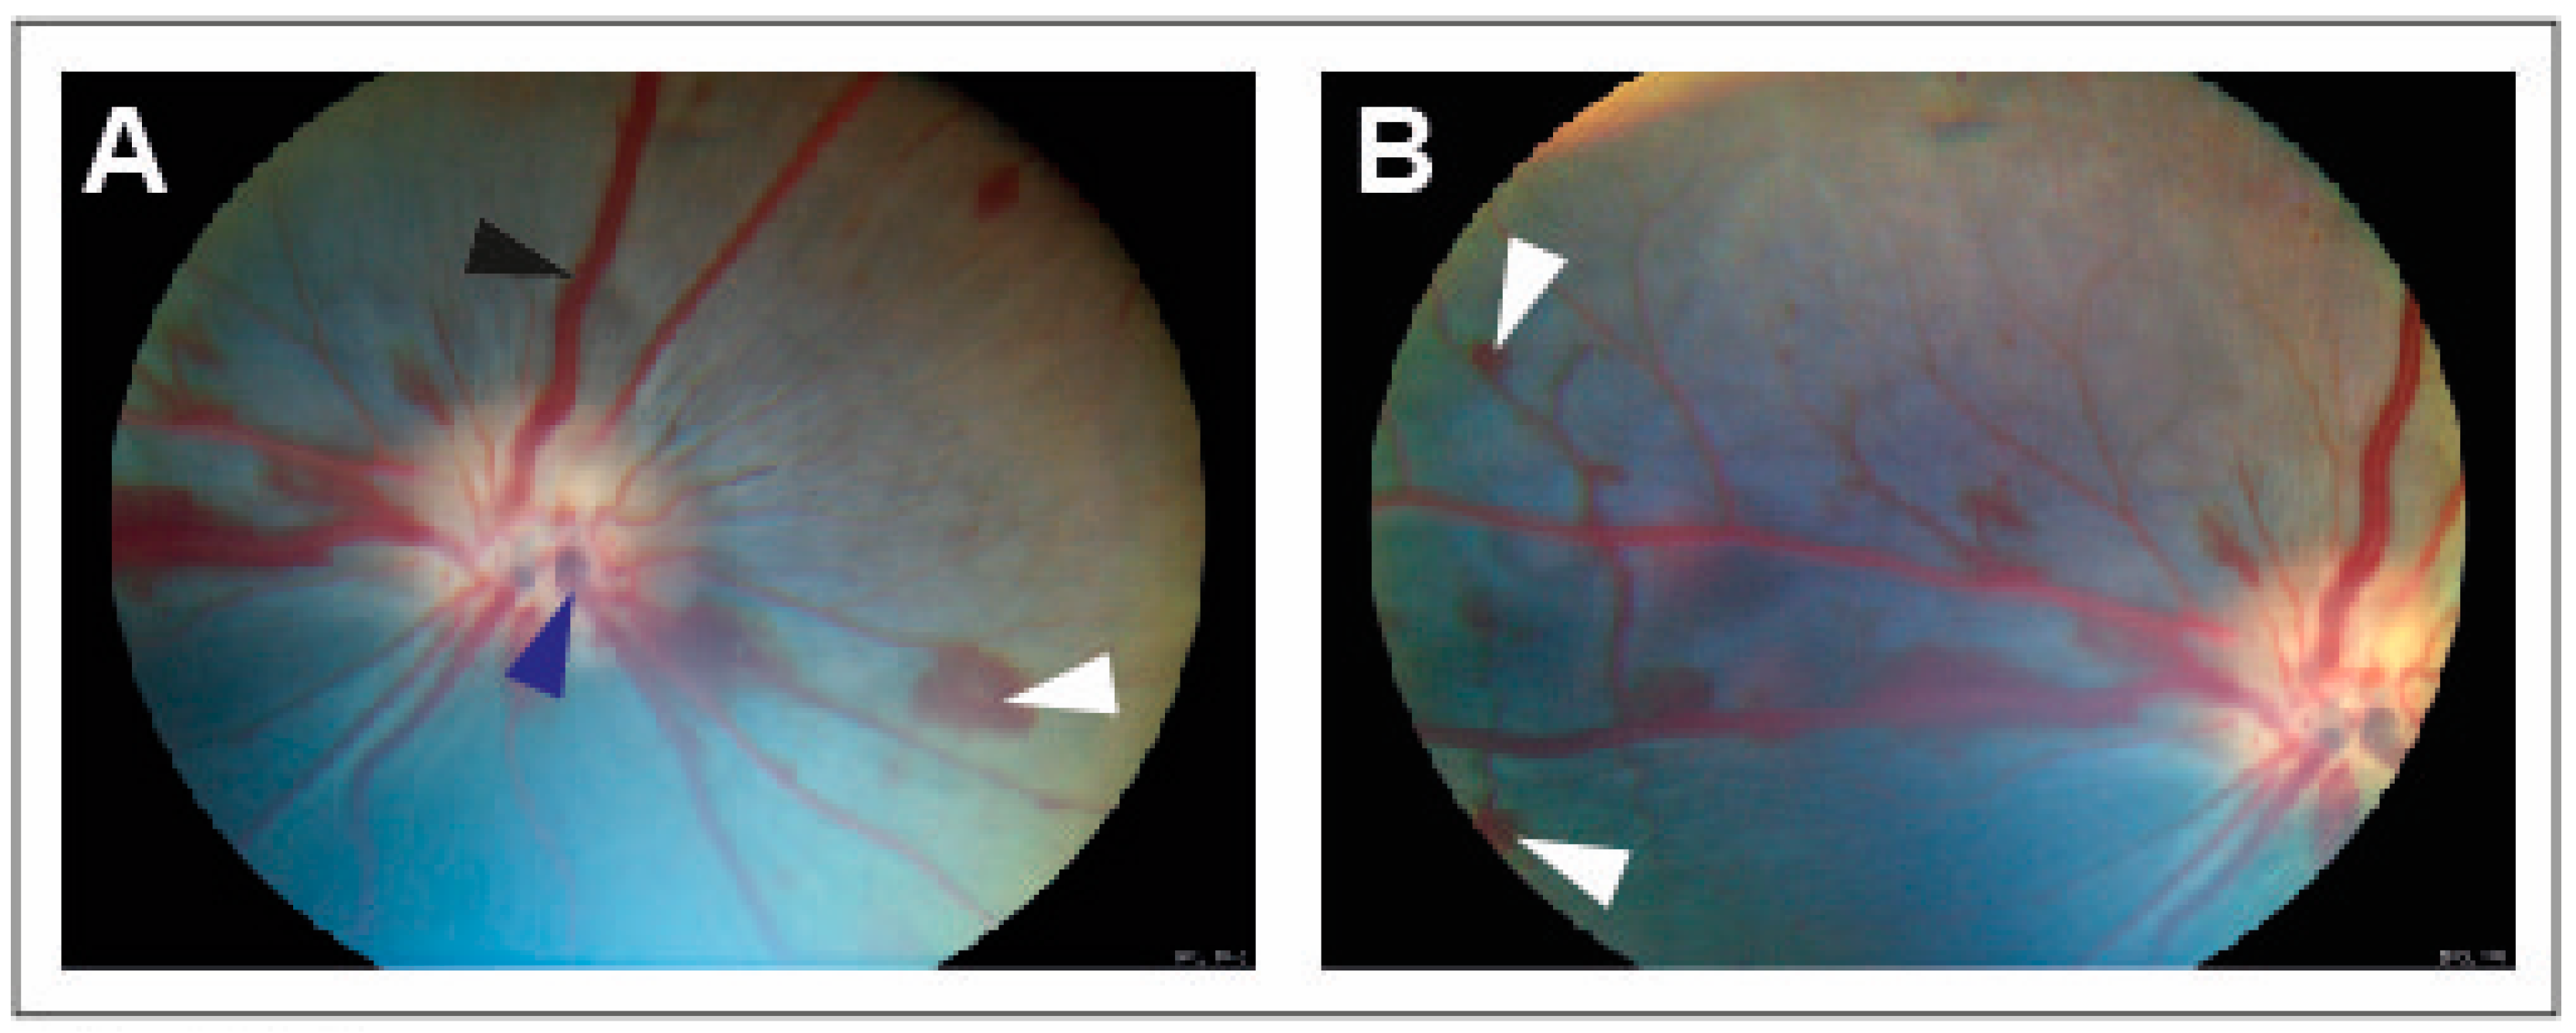

CRVO was successfully induced in all eyes (Figure 1). Angiography confirmed successfully induced CRVO (Figure 2).

Figure 1. Fundus images obtained within 30 min of induced CRVO. (A) Fundus image of experimental CRVO with venous dilation and retinal hemorrhages upstream of the occlusion. White arrow: Retinal hemorrhage. Black arrow: Dilated retinal vein. Dark blue arrow: Site where laser is applied to displace thrombotic material toward the lamina cribrosa. (B) Peripheral view of retinal hemorrhages. White arrow: Retinal hemorrhage.